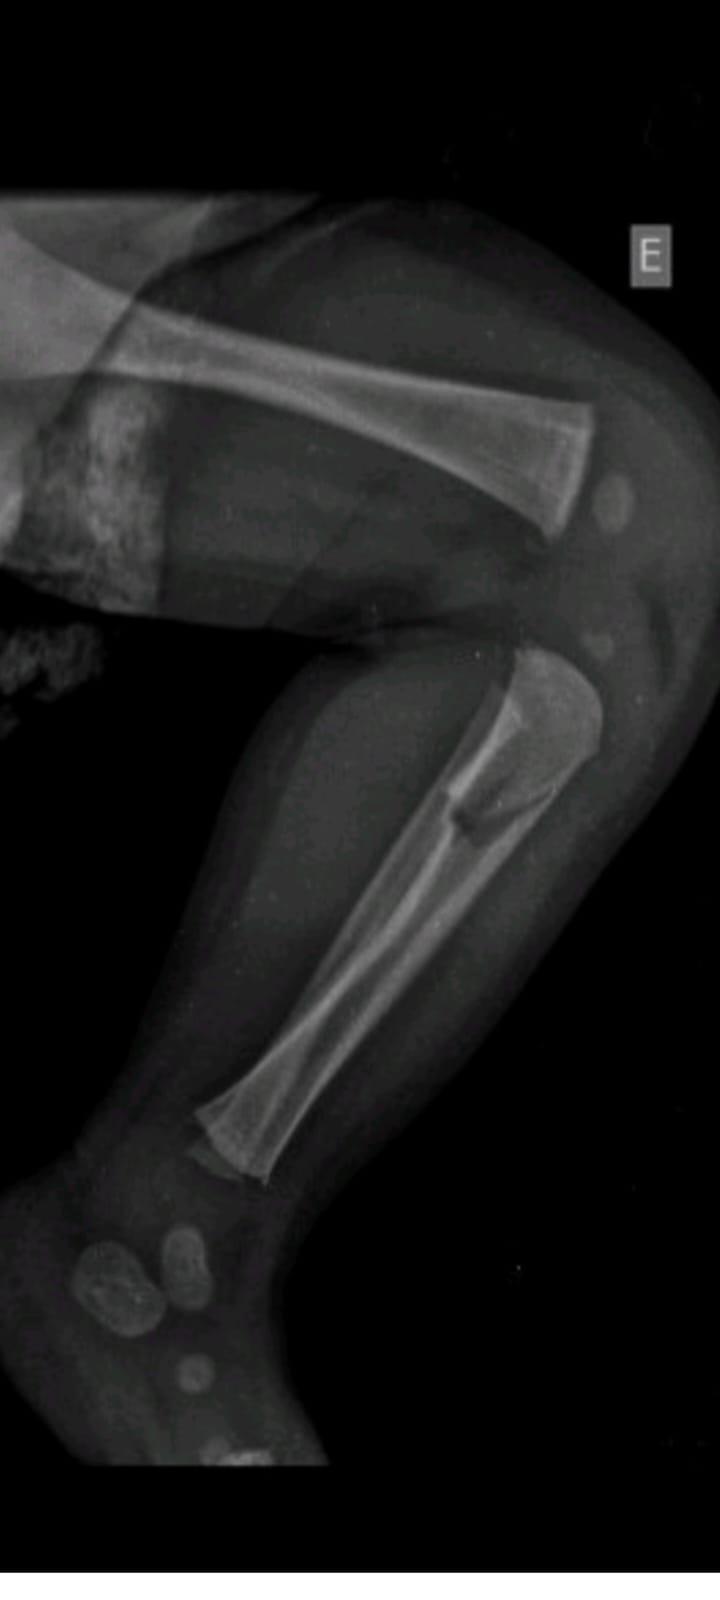

Na manhã desta segunda-feira (07) a 20ª Subdivisão Policial de Toledo divulgou o resultado das investigações acerca de uma tentativa de homicídio praticada contra um bebê, na época com aproximadamente 40 dias, onde os pais do infante eram os suspeitos.

O caso ocorreu no início do mês de julho, sendo os pais investigados inicialmente presos temporariamente por 30 dias.

Durante este período as investigações transcorreram e foi possível reunir ainda mais evidências do envolvimento dos pais da criança no caso, fato este que ensejou representação pela Prisão Preventiva, a qual foi determinada pelo Poder Judiciário, seguindo os pais da criança (21 e 22 anos de idade) agora presos por tempo indeterminado enquanto aguardam o andamento do Processo.

O Delegado Rodrigo Baptista Santos disse que "a postura dos investigados em sustentar uma versão absurda para os fatos constatados, dizendo que não tinham notado os hematomas, os quais surgiram repentinamente, acreditando serem reações alérgicas de uma picada de mosquito, caíram por terra com os Laudos e exames que atestam a gravidade das lesões e o risco a vida do qual o infante foi exposto".